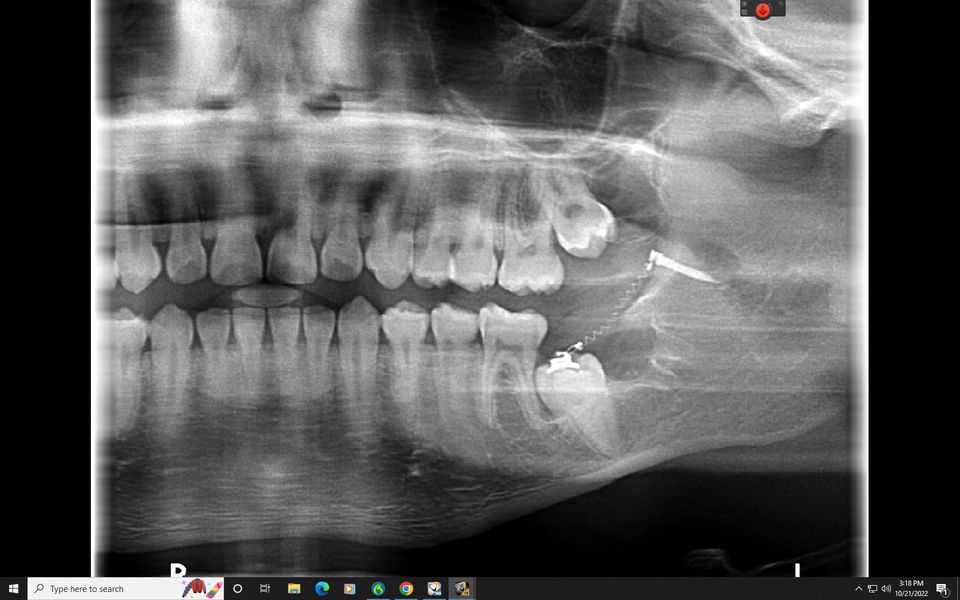

Teeth sometimes do not have the ability to erupt normlaly into the mouth. Dr. Lenk can use braces or even just springs to guide these stubborn teeth into the mouth! 4 years of higher education in orthodontics and 15 years in business, Dr. Lenk knows all the recipes to move teeth 🙂